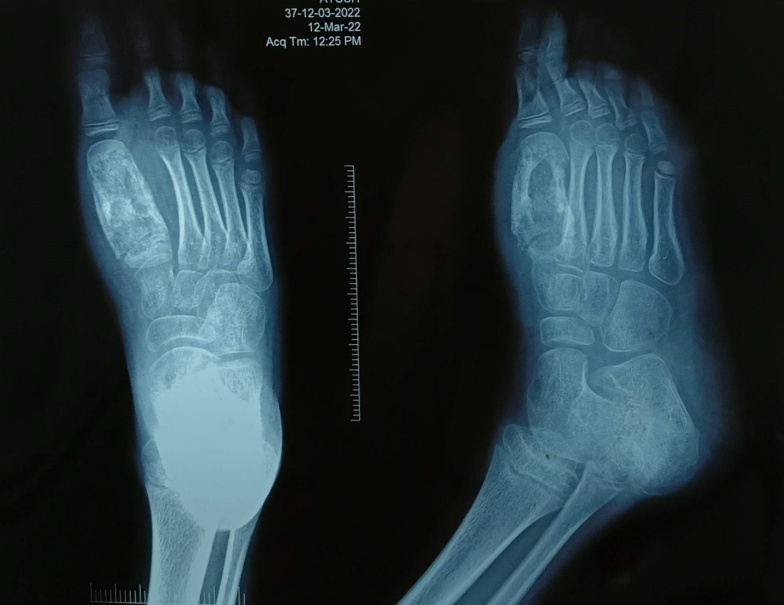

On admission, routine blood investigations like complete blood count, erythrocyte sedimentation rate, bleeding time, clotting time, liver function test, kidney function test and viral markers were sent. His erythrocyte sedimentation rate was mildly raised, but his white blood cell count and other blood tests were within the normal range. A tuberculin skin test was positive, and a chest radiograph was normal. A radiograph of the right foot revealed a centrally placed lytic lesion with an eccentrically located sclerotic lesion in the first metatarsal. The cortices of the first metatarsal were thickened, and the diaphysis was wider than in the other metatarsals. Magnetic resonance imaging study of right foot revealed an altered signal intensity of the first metatarsal, corresponding to the osteolytic lesion with intraosseous abscess, loss of cortex at places and periosteal reaction with fluid signal intensity along the first metatarsal; fluid signal intensity was also noted in the surrounding soft tissue over dorsum and plantar aspect of foot.